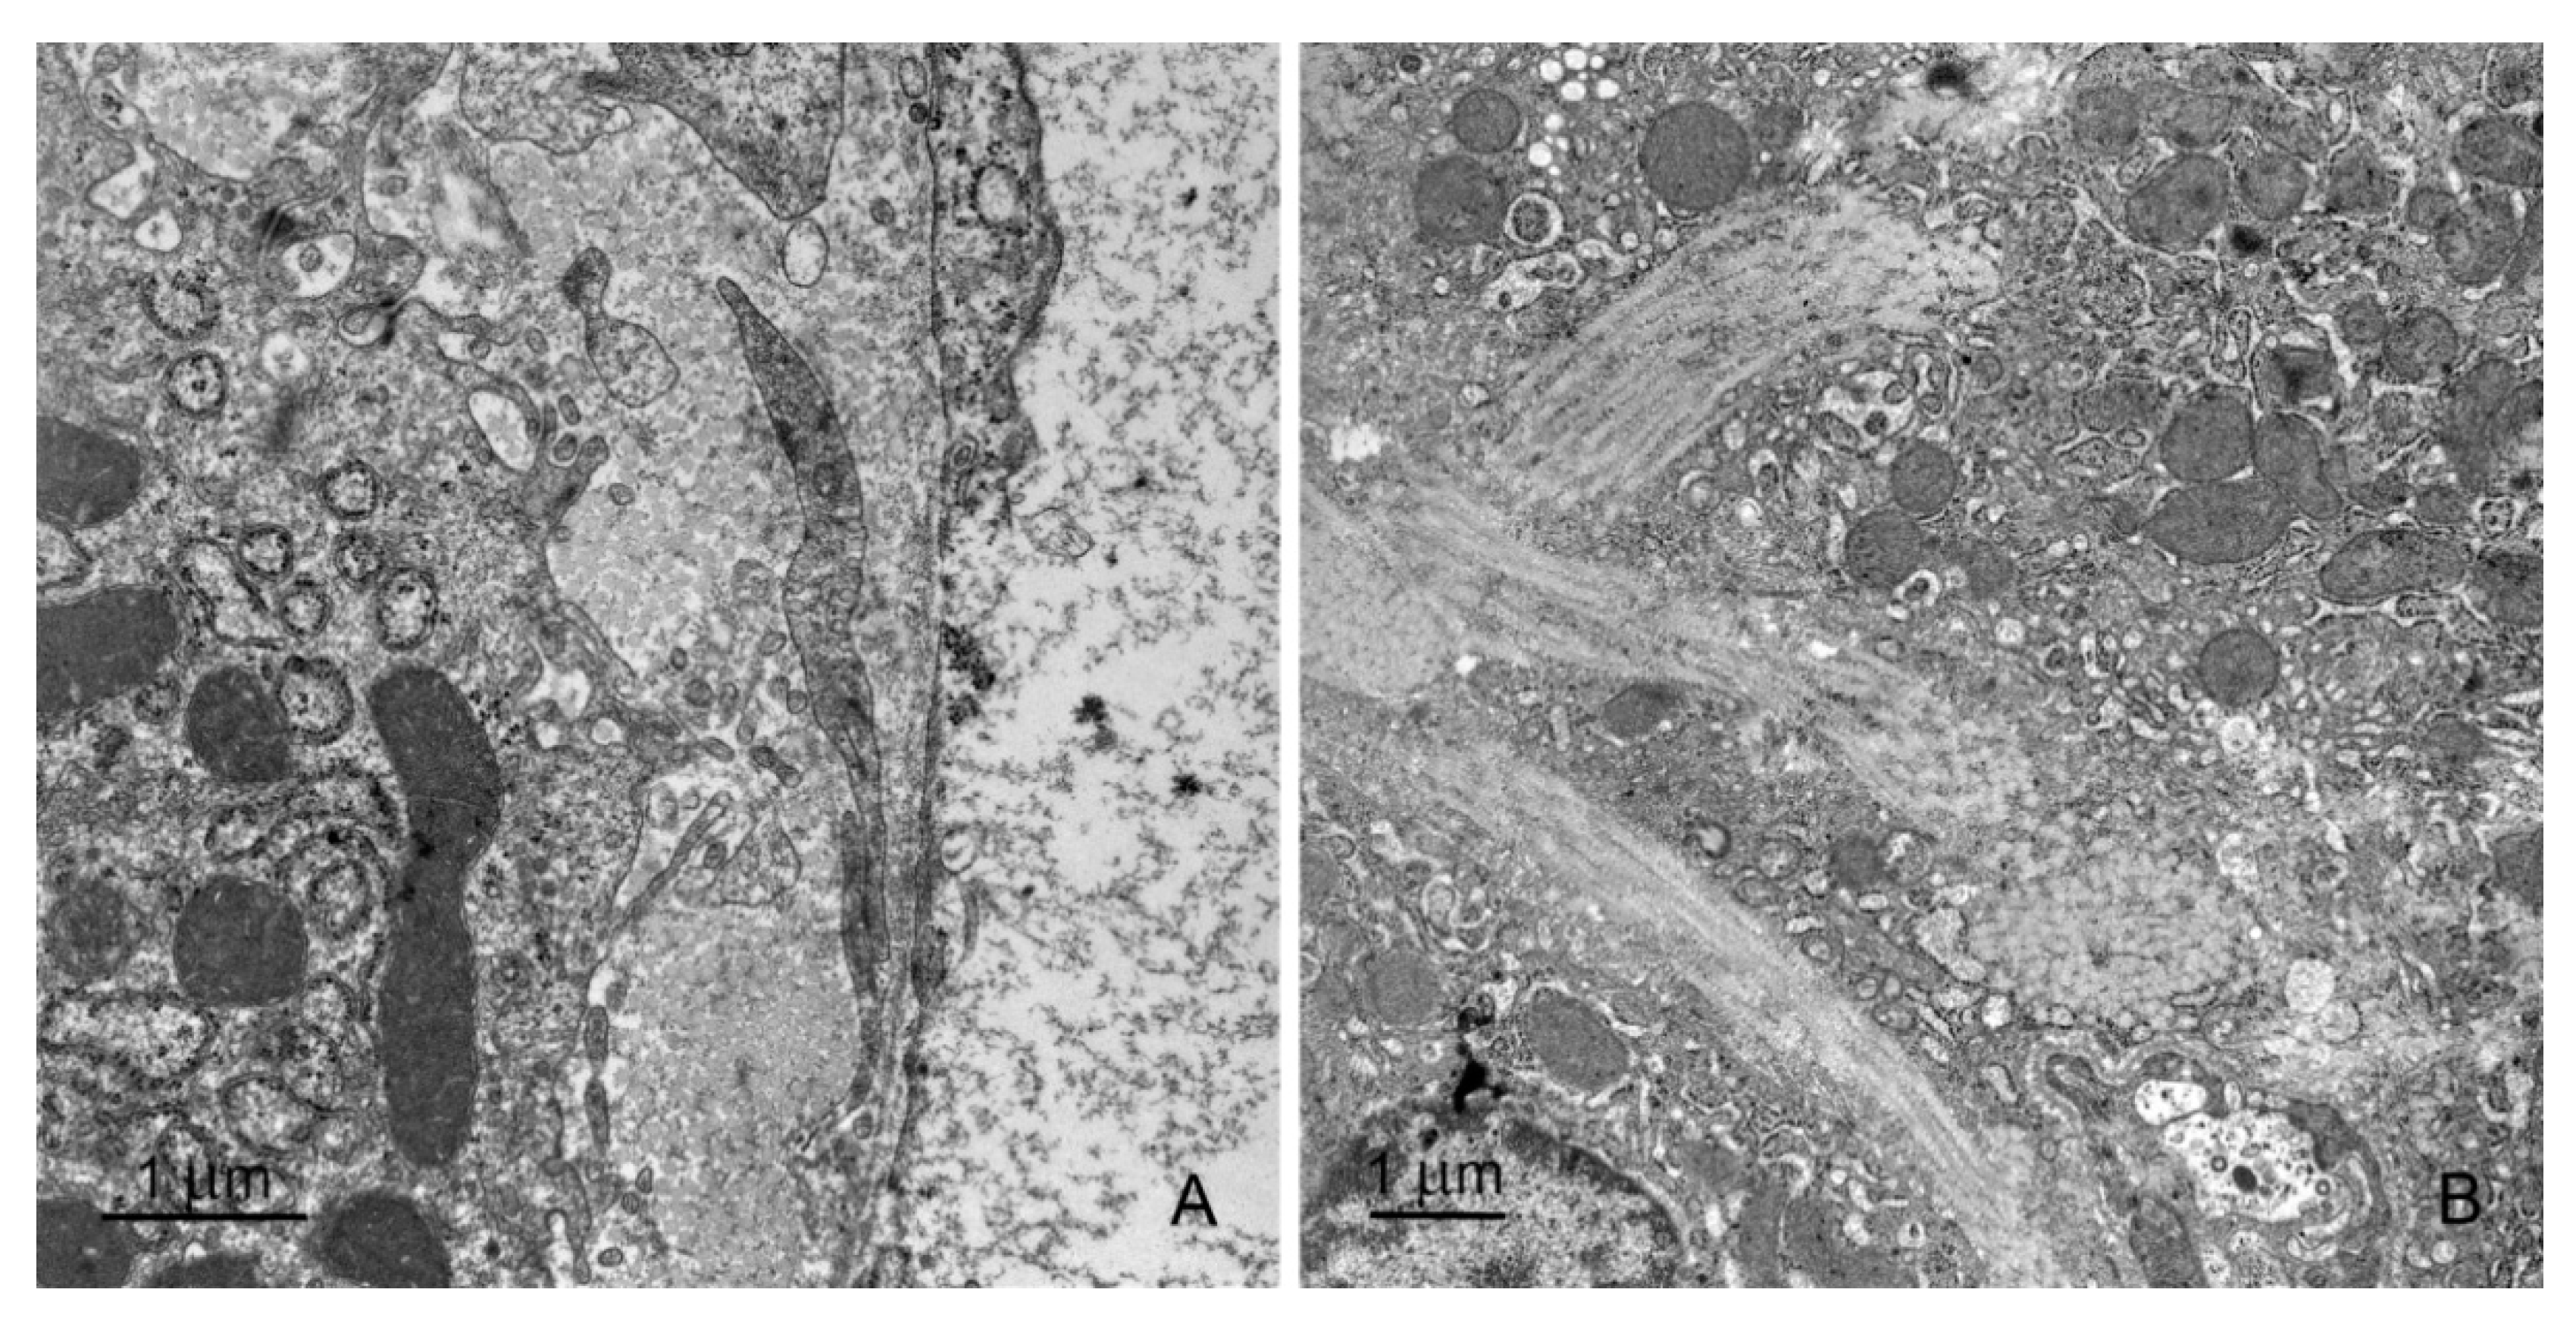

2.2. Ultrastructural Study

2.2.1. Hepatocytes

2.2.2. Sinusoids and Perivascular Species